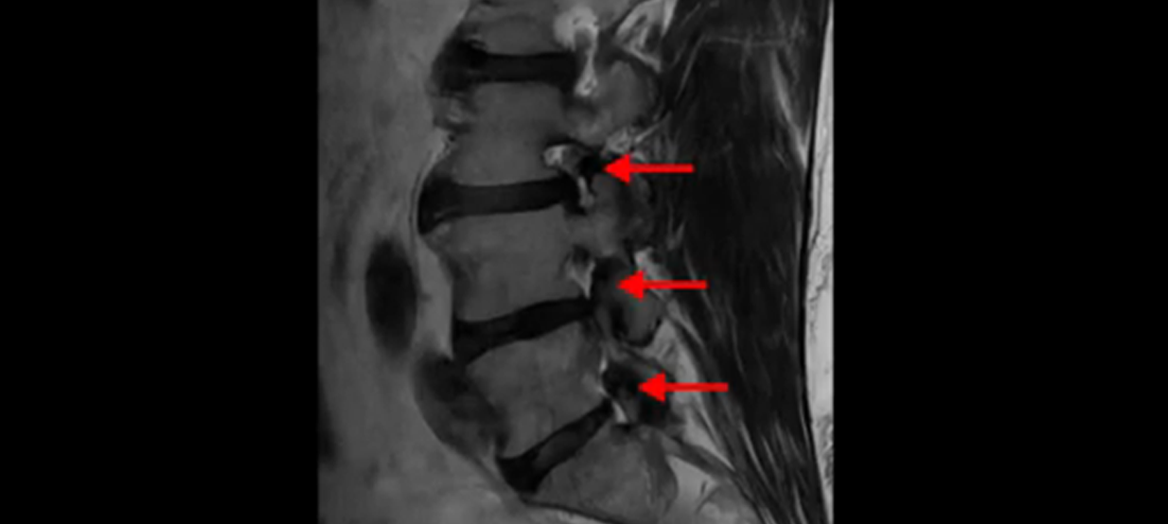

이분 MRI를 잠깐 보실까요? 보시면 두 마디가 특히 안 좋은데 3번 4번 디스크가 터져서 흘러 내려 있습니다.

또 4번 5번에는 협착으로 척추관이 많이 좁아져 있습니다.

또 왼쪽 신경 가지들이 빠져 나가는 신경구멍들이 여러 마디가 좁아져 있습니다.

이런 이유들 때문에 왼쪽 엉덩이부터 종아리, 발가락까지 저리고 아픈 겁니다. 그래서 서둘러 병원에 가셨는데요. 그래서 서둘러 병원에 가셨는데요. 여러분이 꼭 아셔야 할 게 이렇게 다리가 심하게 저리고 아프면 X-ray만 찍을 게 아니고 MRI를 찍어 보시는 게 맞습니다. X-ray로는 디스크가 터졌는지 신경구멍이 좁아진 협착이 있는지를 정확히 할 수가 없습니다. 그래서 이분은 당장 아픈데 해결이 안 되니까 제주도에서 유명하다는 한의원으로 갔습니다.